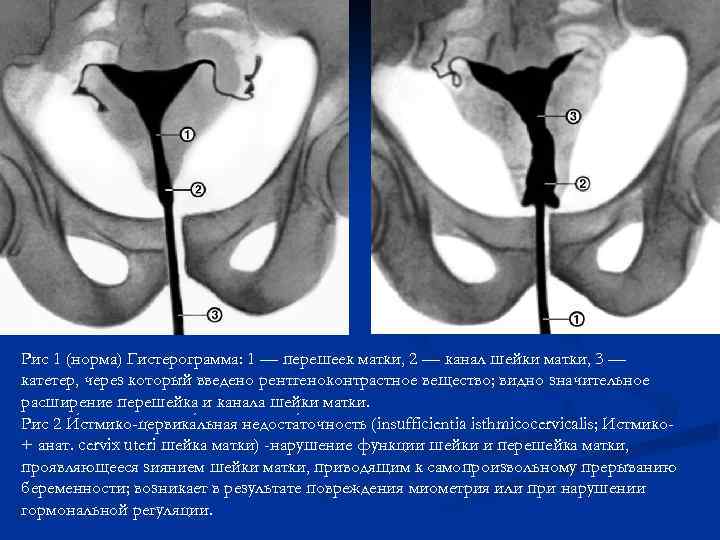

Рис 1 (норма) Гистерограмма: 1 — перешеек матки, 2 — канал шейки матки, 3 — катетер, через который введено рентгеноконтрастное вещество; видно значительное расширение перешейка и канала шейки матки. Рис 2 И стмико-цервика льная недоста точность (insufficientia isthmicocervicalis; Истмико+ анат. cervix uteri шейка матки) -нарушение функции шейки и перешейка матки, проявляющееся зиянием шейки матки, приводящим к самопроизвольному прерыванию беременности; возникает в результате повреждения миометрия или при нарушении гормональной регуляции.

Рис 1 (норма) Гистерограмма: 1 — перешеек матки, 2 — канал шейки матки, 3 — катетер, через который введено рентгеноконтрастное вещество; видно значительное расширение перешейка и канала шейки матки. Рис 2 И стмико-цервика льная недоста точность (insufficientia isthmicocervicalis; Истмико+ анат. cervix uteri шейка матки) -нарушение функции шейки и перешейка матки, проявляющееся зиянием шейки матки, приводящим к самопроизвольному прерыванию беременности; возникает в результате повреждения миометрия или при нарушении гормональной регуляции.